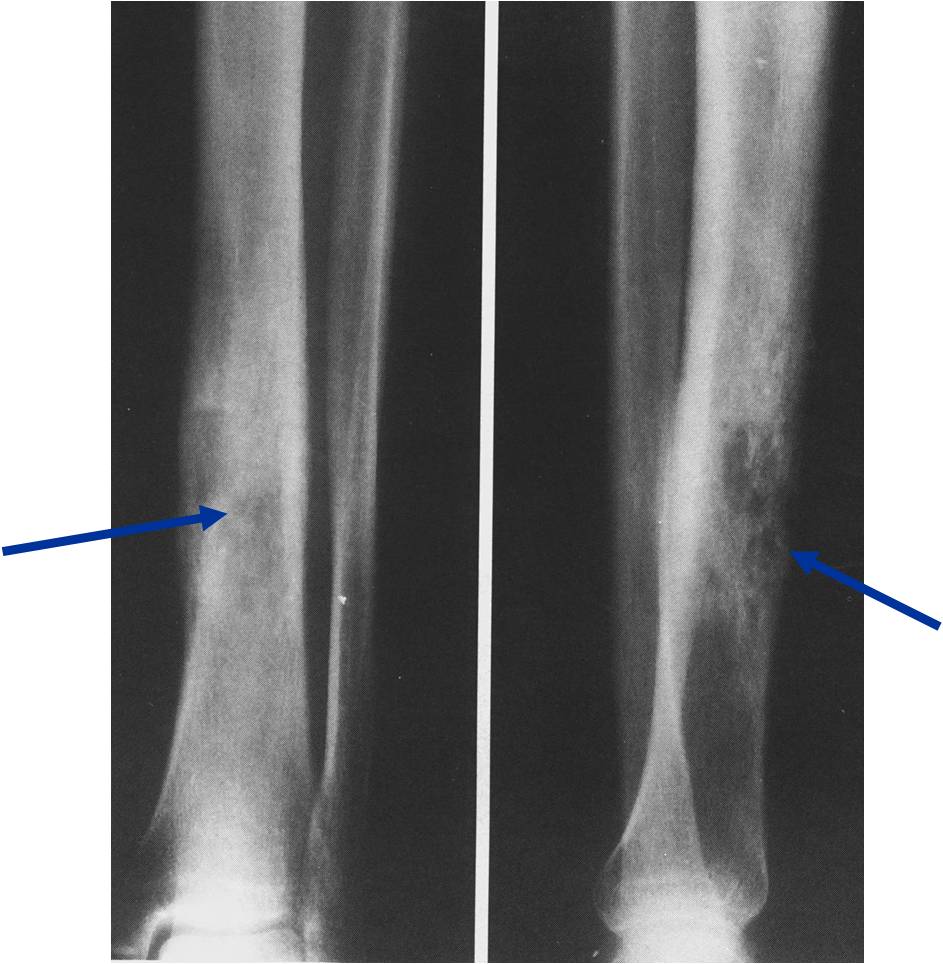

Permeative Moth eaten Lesion

Permeative Lesion

- Permeative or moth eaten bone destruction (55%)

- Geographic (11%); Blow out (1%); Blastic (2%); Normal XR (5%)

- Metadiaphysis (75%)

- Periosteal reaction—may look benign

- Interrupted or solid single layer (66%)